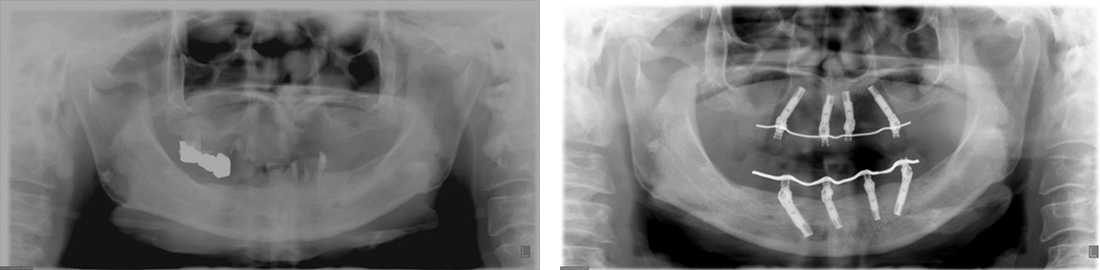

インプラント症例 Case3

Treatment cases

Before

After